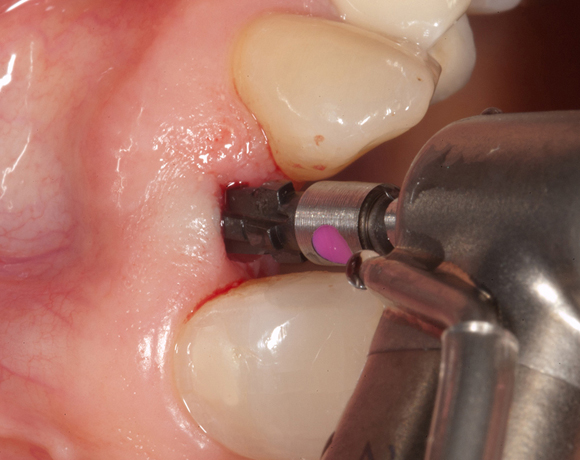

Zeramex T Implantat für Zahn 22

Im vorliegenden Patientenfall musste der Zahn 22 nach erfolgloser Endodontie entfernt werden. Die Nachbarzähne waren kariesfrei, es wurde eine Marylandbrücke (eine Brücke mit zwei Flügelchen, die palatinal an den Nachbarzähnen verklebt werden) oder ein Implantat besprochen. Die Patientin hat sich für ein Vollkeramikimplantat entschieden. In der Diashow wird der operative Eingriff bis zur fertigen Krone gezeigt. Die Einheilzeit betrug drei Monate.